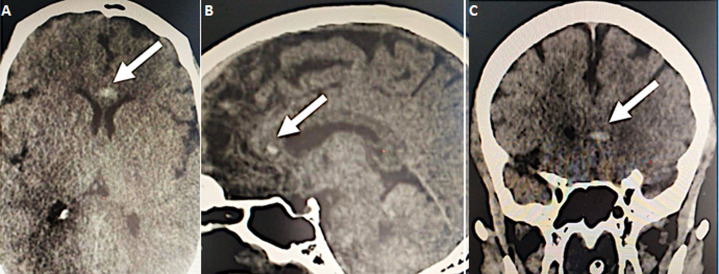

Further investigations were conducted to explore hepatic dysfunction: negative hepatitis serologies and autoimmune tests. Blood paracetamol level was normal. Factor V level was normal of 89%. Our therapeutic care was based on Ceftriaxon (2g per day) and Moxifloxacin (400 mg, twice a day), proton pump inhibitors, vitamin C, Vitamin D and Zinc. The patient received fresh frozen plasma transfusion, N-acetyl-cystein which led to a stabilization of his hemostasis levels. Preventive anti-coagulation was introduced in the treatment. The evolution was marked with a worsening of his respiratory status and renal function. Hemodialysis was indicated and realized. Venous doppler of lower limbs was conducted and revealed left deep venous thrombosis. Echocardiography showed right ventricle dysfunction as a sign of acute pulmonary embolism which was confirmed with CT angiogram (Figure 1, Figure 2). Curative doses of unfractionned heparin were introduced. Sedation was reduced after two weeks; however, the patient did not regain consciousness. Cerebral CT was performed and revealed a spontaneous corpus callosum rostrum hematoma (Figure 3).

Figure 3.

A) hematoma of the corpus callosum rostrum, axial view (white arrow); B) hematoma of the corpus callosum rostrum, sagittal view (white arrow); C) subocclusive pulmonary embolism, sagittal view (white arrow)